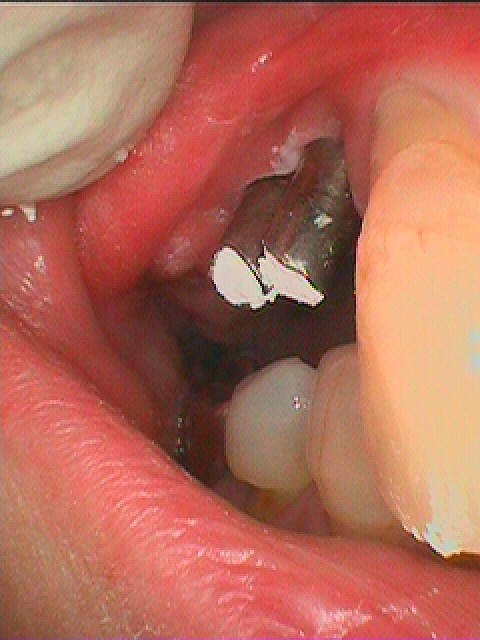

口腔内です

6番部は歯周病にて保存不能

手前のインプラントも角度が悪そうです

このようにかなりインプラントが近接しています

被せも本来の歯の形態とは似つかわしくない状態でした